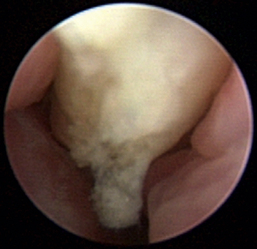

Figure 19-30 Feline nasal Cryptococcus with ulceration and granuloma formation.

Aspergillus fumigatus is the most common canine fungal rhinitis.26 Chronic, unilateral mucopurulent to mucohemorrhagic nasal discharge is often reported. Serologic,3 CT, and MRI27 findings lack sensitivity and specificity, respectively, for reliable diagnosis of sinonasal aspergillosis. Rhinoscopic visualization and histopathologic evaluation are necessary for diagnosis confirmation. The classic fungal rhinitis lesion is a green-gray, whitish, necrotic plaque in the midcaudal nasal cavity. Regional turbinate reactive hyperplasia can be present, making the visual examination findings heterogeneous at best (Figures 19-31 through 19-33). The frontal sinuses should be examined in patients with suspected fungal rhinitis because treatment of all fungal mats is necessary for disease resolution. Sinusoscopy, sinusotomy, or both are often recommended to access and debride frontal sinus fungal mats and for antifungal instillation.28 Several treatment protocols have been described employing either single-agent sinonasal lavages or systemic antifungal therapy, depending on the fungus. We believe rhinoscopic debridement and flushing to remove fungal plaques improves the response to local treatment.

image

Figure 19-31 Canine nasal aspergillosis with mucus, hyperplasia, and ulceration.

Figure 19-32 Canine nasal aspergillosis with ulceration as the source of epistaxis.

Figure 19-33 Canine nasal aspergillosis fungal mats in the caudal nasal cavity.